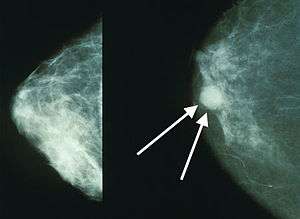

Mammograms showing a normal breast (left) and a breast with cancer (right, white arrows). | |

A clinical or self breast exam involves feeling the breast for lumps or other abnormalities. Clinical breast exams are performed by health care providers, while self breast exams are performed by the person themselves.[100] Evidence does not support the effectiveness of either type of breast exam, as by the time a lump is large enough to be found it is likely to have been growing for several years and thus soon be large enough to be found without an exam.[101][102] Mammographic screening for breast cancer uses X-rays to examine the breast for any uncharacteristic masses or lumps. During a screening, the breast is compressed and a technician takes photos from multiple angles. A general mammogram takes photos of the entire breast, while a diagnostic mammogram focuses on a specific lump or area of concern.[103]